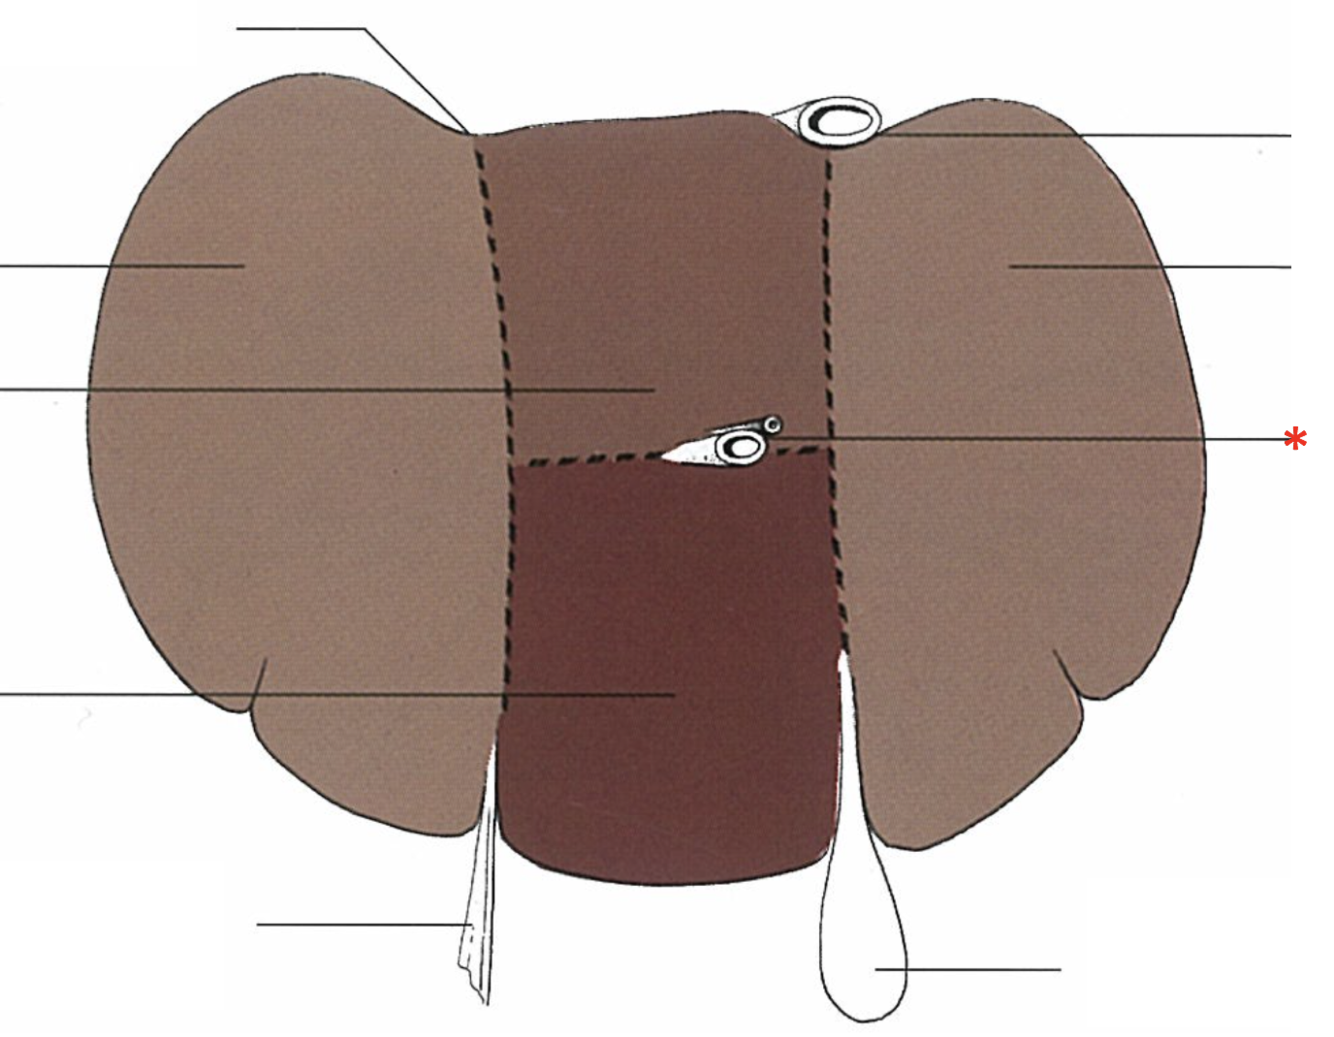

Porta hepatis

- With v. portae et a. hepatica

Lobus caudatus

Lobus quadratus

Lobus hepatis sinister medialis

Lobus hepatis dexter medialis

Lobus hepatis dexter lateralis

Proc. caudatus

V. portae

Proc. papillaris

Lobus hepatis sinister lateralis

Impressio renalis

What is shown? Give the Aspect.

Liver of a Cat

Fascies visceralis